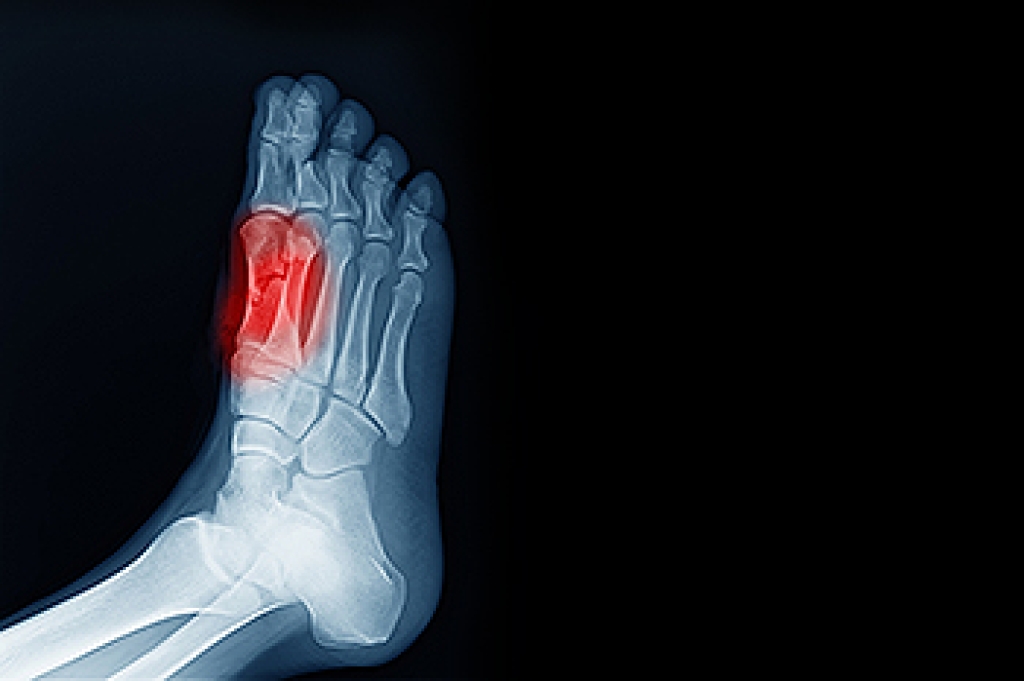

If over-the-counter inserts don’t work for you or if you have a more severe foot concern, it is possible to have your podiatrist prescribe custom orthotics. These high-quality inserts are designed to treat problems such as abnormal motion, plantar fasciitis, and severe forms of heel pain. They can even be used to help patients suffering from diabetes by treating foot ulcers and painful calluses and are usually molded to your feet individually, which allows them to provide full support and comfort.